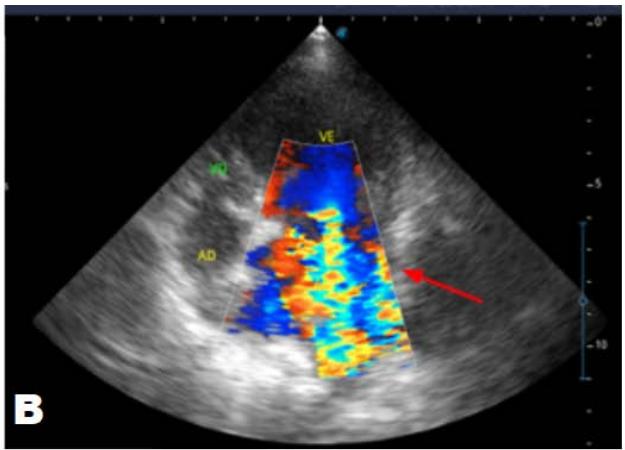

One year later, the animal returned for a new evaluation, repeating the ECHO (Figure 2), which showed the progression of the increase in the left atrium. The electrocardiogram (ECG) (Figure 3) shows baseline sinus arrhythmia with the presence of a premature ventricular complex (Figure 4). Owners report drowsiness, hyporexia, and syncope. However, they did not present tiredness or cough. Blood pressure was 80 mmHg.

Figure 2: Echocardiogram (2022): observed increase in the left atrium and ventricle; thickened/degenerated mitral valve (A); observed in a Doppler study, turbulent systolic flow within the left atrium, characterizing significant mitral valve insufficiency (B); systolic turbulent flow within the right atrium, representing mild tricuspid valve insufficiency (C); hemodynamic assessment - maximum velocity gradient mitral regurgitation: $3.51\mathrm{m / s} / 49.22\mathrm{mmHg}$; observed left ventricular diastolic dimension above normal limits with normal systolic function parameters, characterizing systolic dysfunction; preserved diastolic function

In 2022, the animal returned for annual exams one year after the diagnosis. The ECHO showed an increase in the left atrium and ventricle, thickened/degenerated mitral valve (Figure 2), preserved diastolic function, and low probability of pulmonary hypertension; the ECG detected an increase in the duration of the P wave and the QRS complex (Figure 3), suggestive of atrial and left ventricular overload, baseline sinus arrhythmia with the presence of a premature ventricular complex.